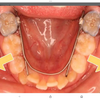

それは下の図です。。

身体は繋がっています。。

全身でバランスとっているんです。

骨盤が歪み、股関節が捻れれば、頭蓋骨も歪み、顎関節が歪むのです。

逆に言えば、骨盤を調整すれば、顎も調整される。。

すると、口内が丸く広くなる。。

それで歯が自分で移動を始めるんです。